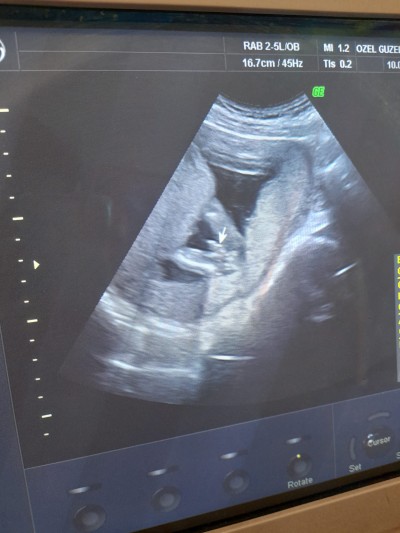

Kizlar 15 haftalıkken gitmiştim erkek dedi ben emin olamadım değişme ihtimali var mı ultrason fotoğrafı bu sizce ne???

Gebelik haftası 15+5 haftalık

Bacak arası bu sanırım canım ama pek seçemedim ben testis gibi duruyor ama rabbim hayırlı evlat etsin inşallah

Aminn Allah razı olsun ama bazen kordon da diyebiliyorlar ya o yüzden pek emin olamıyorum

Daha küçük zaten canım değişme ihtimali var bir ay dan daha kesin olur cinsiyeti rabbim gönlüne göre verir inşallah ")